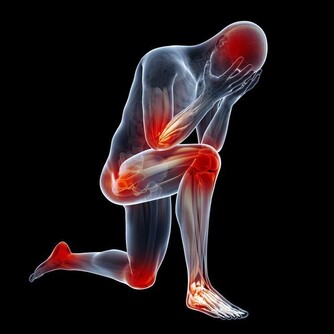

2、加陳醋:促進血液循環、緩解關節疼痛

生薑泡醋,能夠促進血液循環、增加抵抗力、緩解感冒,還有輔助治療關節炎的作用。